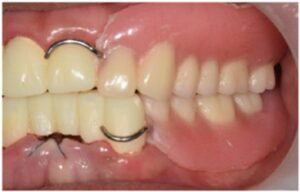

식립해 둔 임플란트가

단단히 결합되기를 기다리는 동안

위아래 앞니 브릿지 보철물 수복을 위한

치아 다듬기를 진행하였으며,

발치 부위의 잇몸이 아물기 전까지

임시치아를 사용하실 수 있도록

도와드렸습니다.

앞니 임시치아에 맞춰

임시틀니를 제작하여

환자분의 무너진 교합 고경을 맞춰드리는

작업을 진행하였는데요.

모든 치료가 마무리된

구강 내 사진과

파노라마 사진인데요.

환자분께서는

그동안 앞니로 식사하시면서

불편감이 많으셨는데

치료 후 양측 저작이 편안하게 잘 되고

전보다 심미적으로 변한 모습에

만족해하셨습니다.